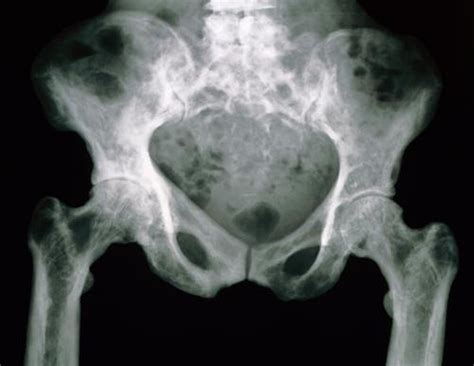

• Imaging tests: X-rays, CT scans, MRI, and bone scans can help visualize the affected bones and assess the extent of the disease.